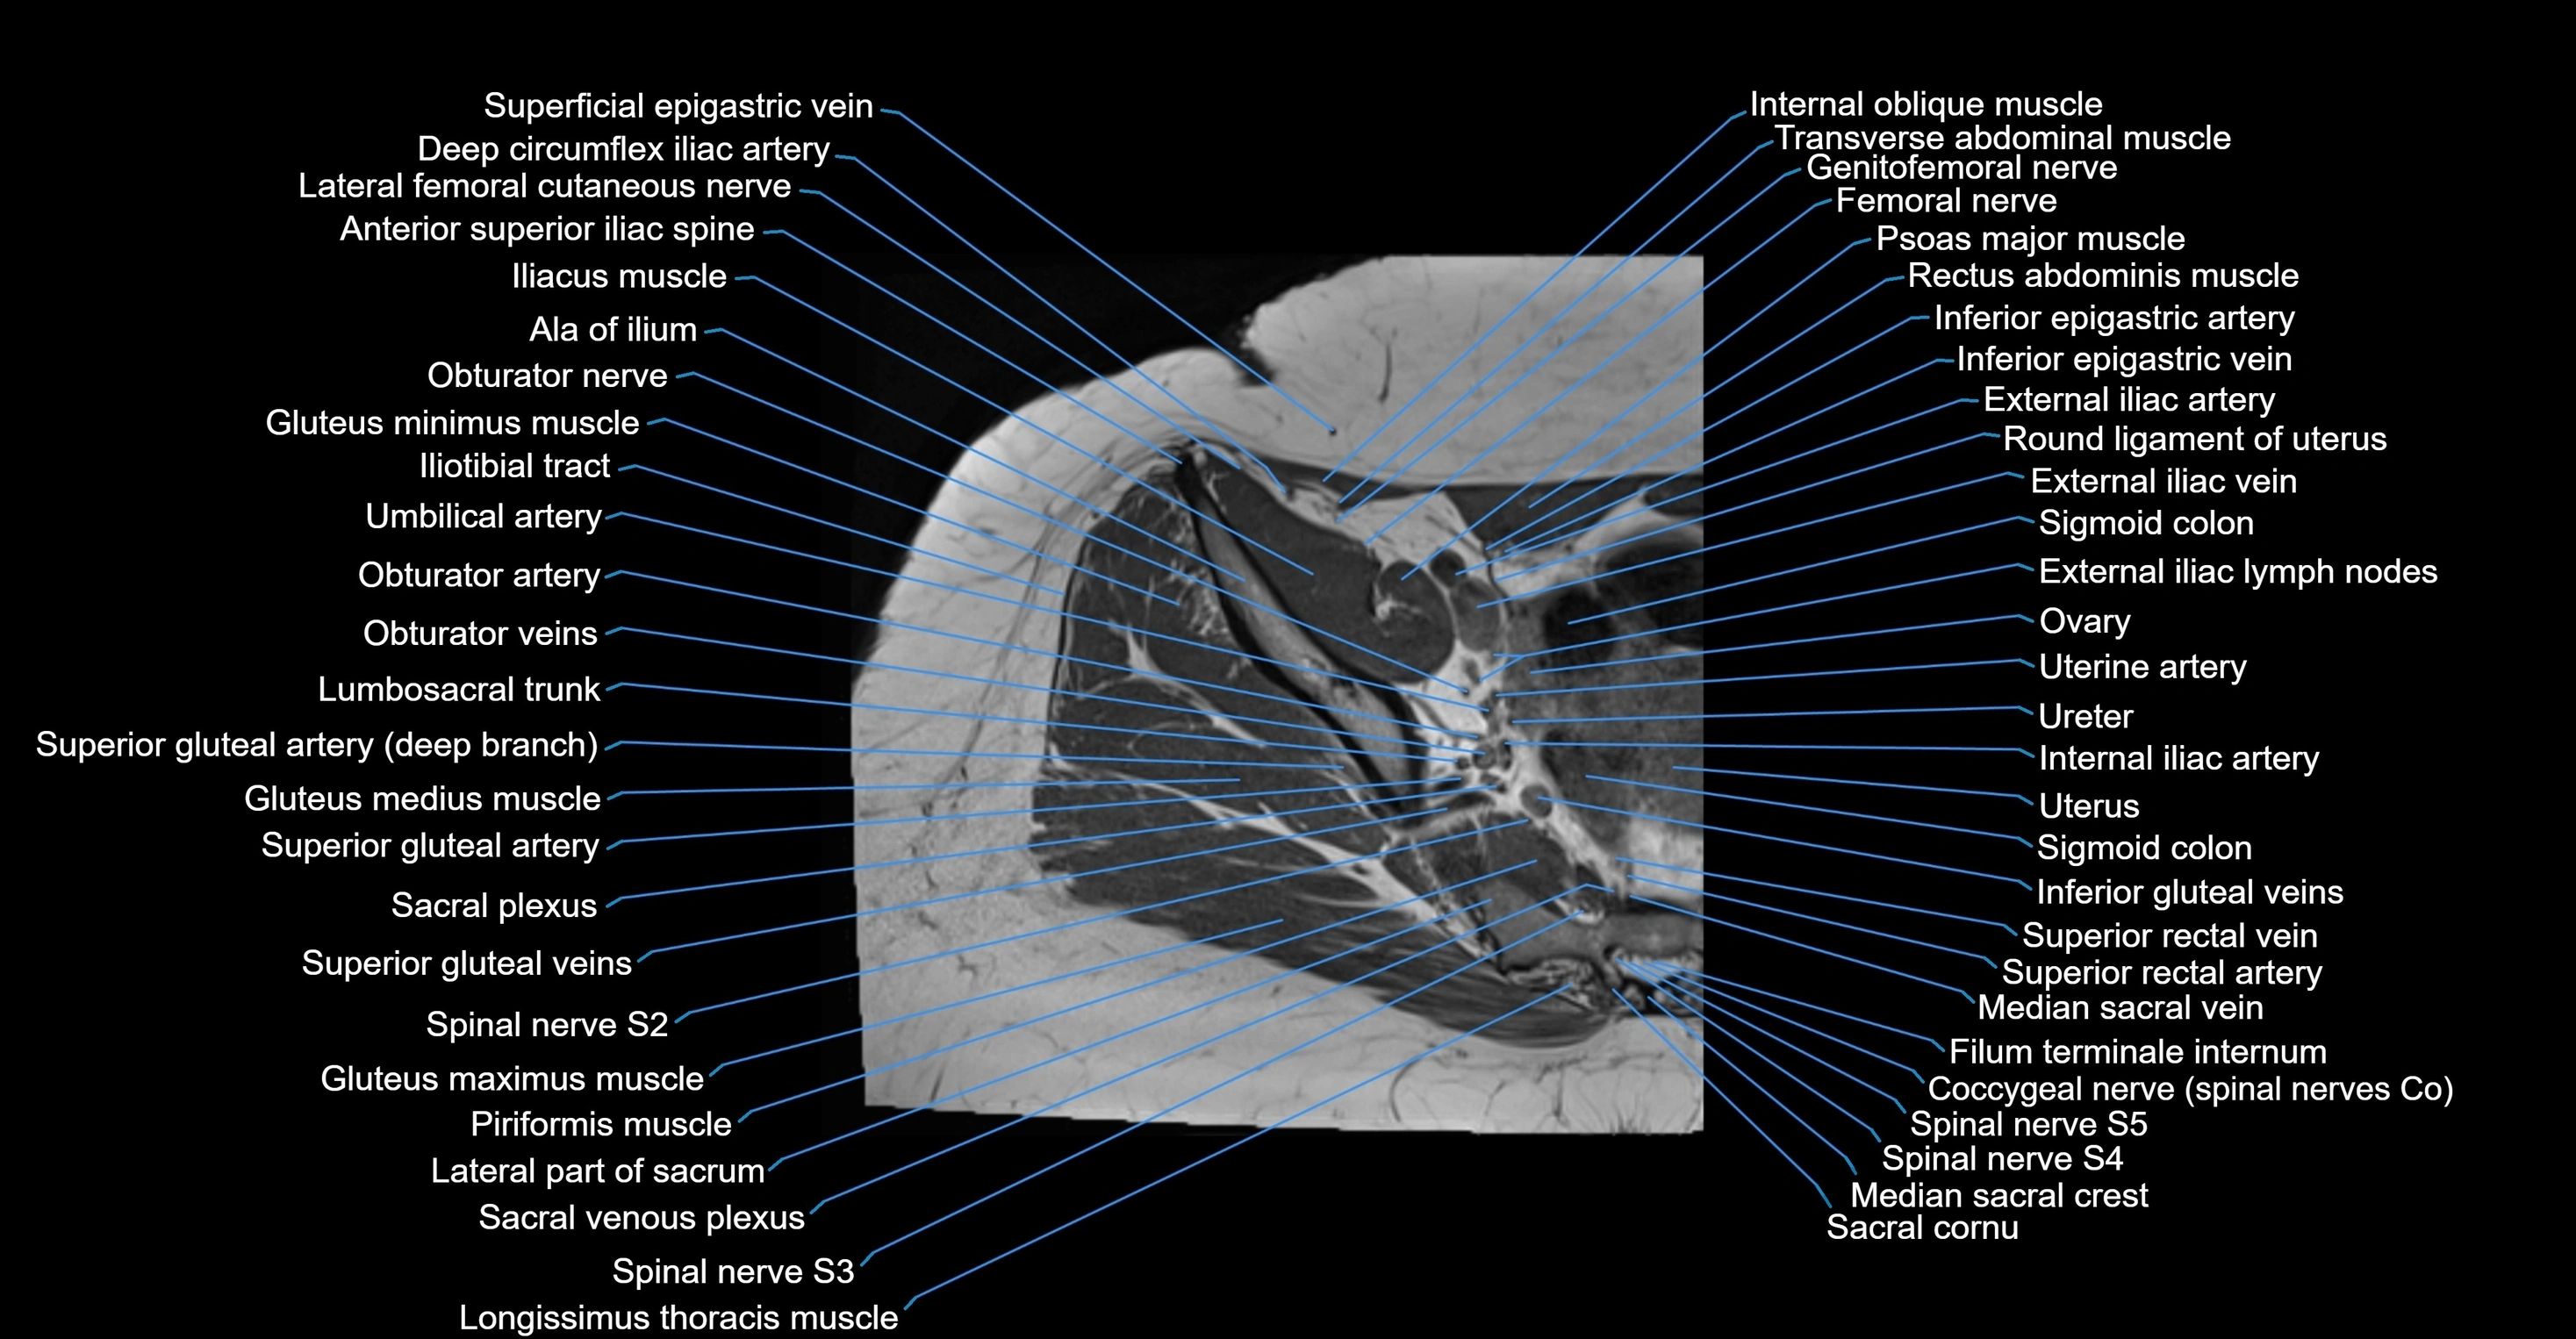

- Ala of ilium (wing of ilium)

- Coccygeal nerve

- Coccygeal plexus

- Common iliac lymph nodes

- Common iliac vein

- Deep circumflex iliac artery

- External iliac artery

- External iliac lymph nodes

- External iliac vein

- Femoral nerve

- Filum terminale internum

- Genitofemoral nerve

- Gluteus maximus muscle

- Gluteus medius muscle

- Gluteus minimus muscle

- Iliotibial tract

- Ilium bone

- Inferior epigastric artery

- Inferior epigastric veins

- Internal iliac artery

- Internal iliac lymph nodes

- Lateral part of sacrum

- Lumbosacral trunk

- Median sacral crest

- Median sacral vein

- Ovaries

- Psoas major muscle

- Pubic bone

- Round ligament of uterus

- Sacral plexus

- Sigmoid colon

- Spinal nerve S1

- Spinal nerve S2

- Spinal nerve S3

- Spinal nerve S4

- Spinal nerve S5

- Superior gluteal artery

- Superior rectal vein

- Umbilical artery

- Uterine artery

- Uterus